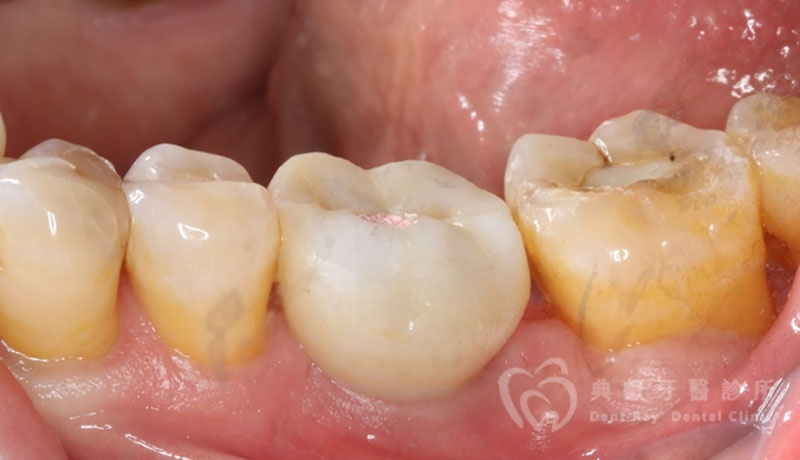

植牙案例一